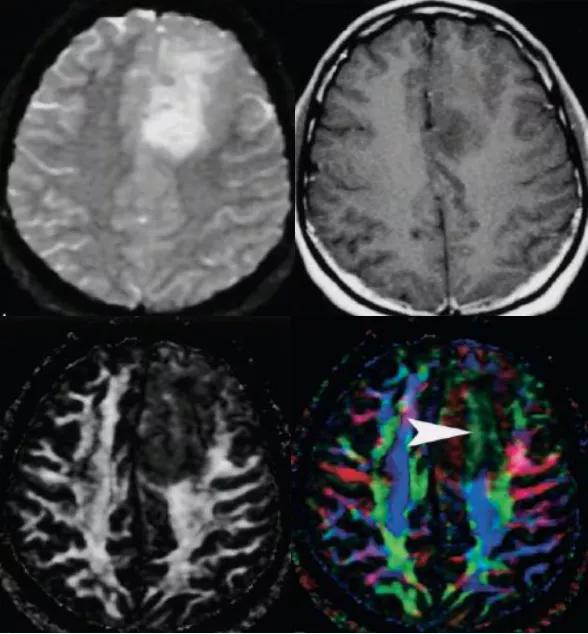

右侧基底区急性期梗死FA值下降,纤维束局部中断

此外,有学者研究发现,与梗死区相联系的同侧内囊、大脑脚和桥脑处的皮质脊髓束FA较对侧显著降低,提示脑梗死后远端的皮质脊髓束可能存在进行性的Wallerian变性,通过对梗死远端皮质脊髓束FA计算判断其变性程度,可以预测患者的运动功能转归。